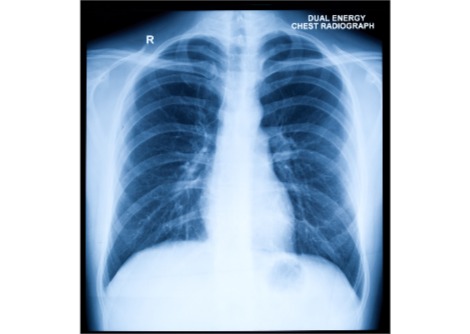

وللحصول على رؤية أكثر شمولاً، حلل أوري ألون وزملاؤه عينات دم جُمعت سابقًا من أكثر من 160 ألف امرأة ، تتراوح أعمارهن بين 25 و31 عامًا، واللواتي حملن مجتمعات بأكثر من 300 ألف حالة حمل. وقد وفرت هذه العينات مجتمعة لمحة عامة عن الجسم كل أسبوع من 20 أسبوعًا قبل الحمل إلى 18 شهرًا بعد الولادة، حيث قدمت كل امرأة بيانات لعدة نقاط زمنية. يقدم هذا النهج رؤى مفيدة حول كيفية تغير الجسم عمومًا أثناء الحمل على مستوى السكان، مع أن تتبع النساء نفسهن في كل نقطة زمنية من شأنه أن يوفر صورة أفضل للمسارات الفردية، كما يقول كريستوف ليز من إمبريال كوليدج لندن.

قام الباحثون برصد التغيرات في 76 مؤشرًا دمويًا، مثل مستويات البروتينات والدهون والأملاح، والتي تشير إلى وظائف الكبد والكلى والدم والعضلات والعظام والجهاز المناعي. ووجدوا أن كل مؤشر من هذه المؤشرات يختلف اختلافًا كبيرًا عن مستويات ما قبل الحمل أثناء الحمل، قبل أن يعود تدريجيًا إلى مستويات ما قبل الحمل أو يتجاوزها قبل أن يستقر عند مستوى ما قبل الحمل.